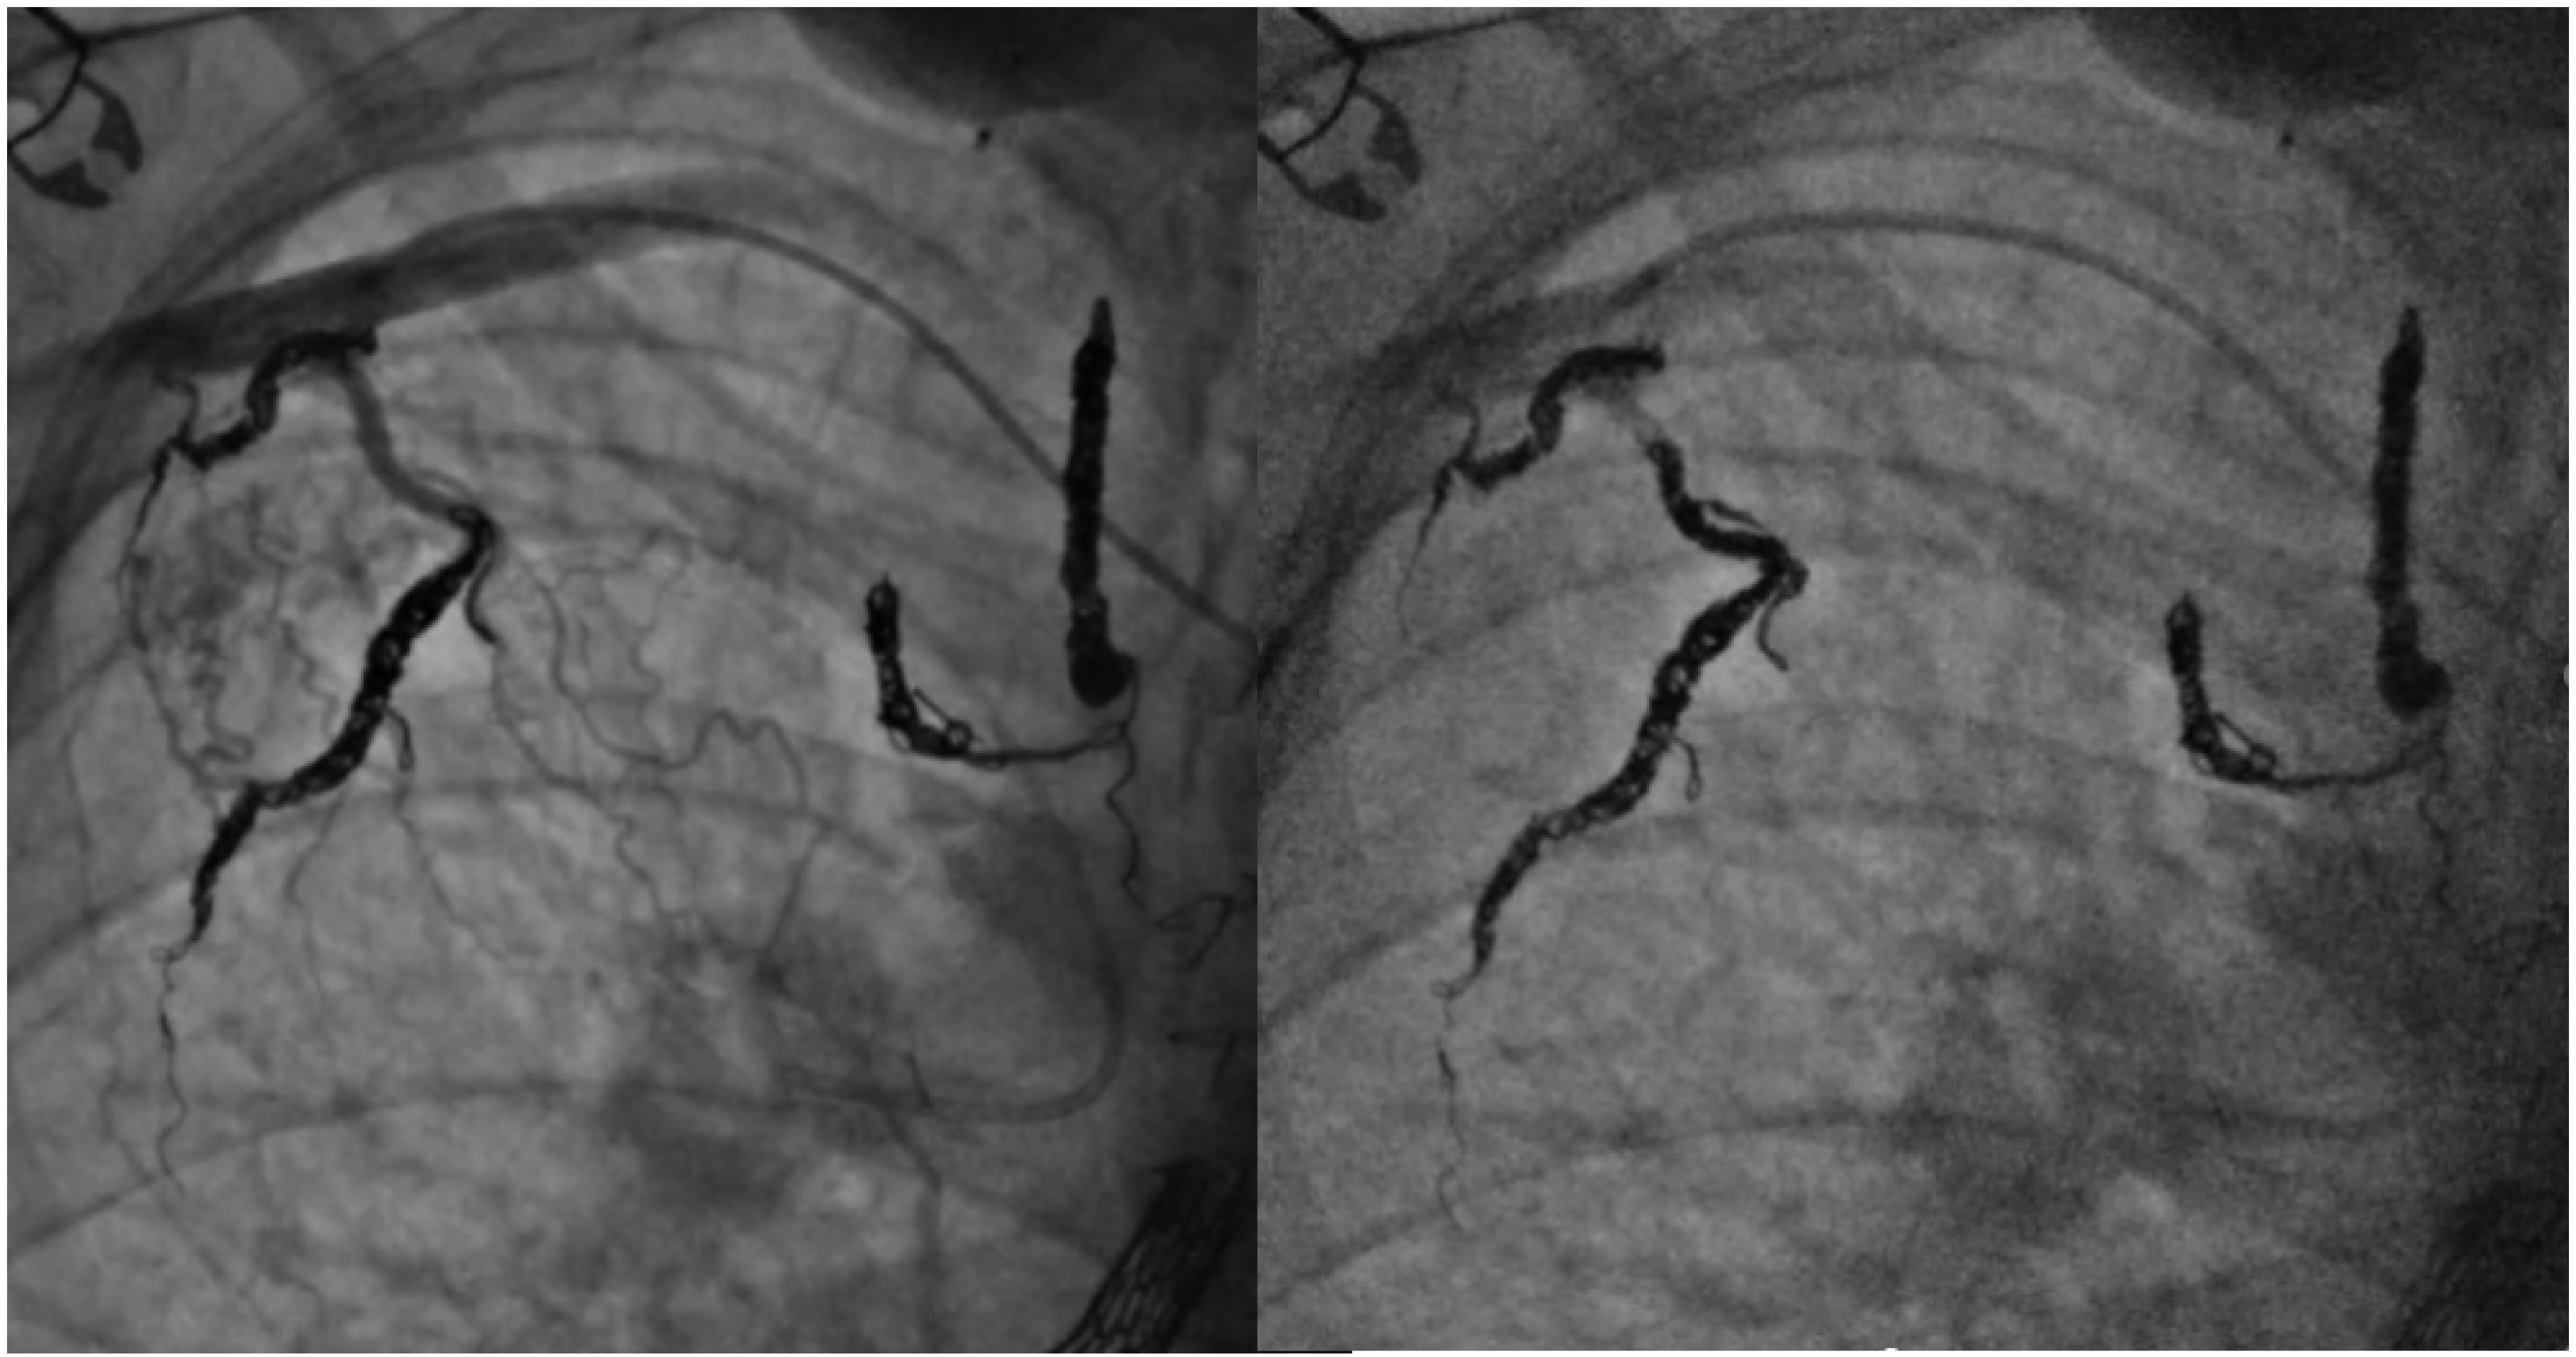

8. Collateral Coil Embolization